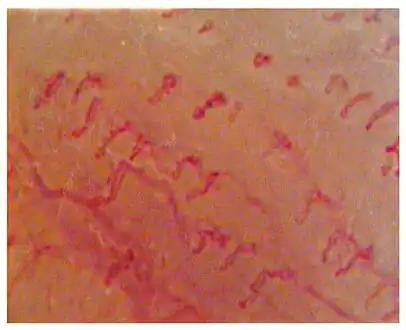

Capillaroscopic evaluation in Burning mouth syndrome

- Burning mouth syndrome - this chronic pain disorder commonly involves the tongue. In reflection of this, some of the synonyms for the condition include tongue-specific terms such as "glossodynia" or "burning tongue syndrome". Burning mouth syndrome is characterized by chronic burning sensation on the tongue and other oral mucous membranes in the absences of any identifiable signs or causes.